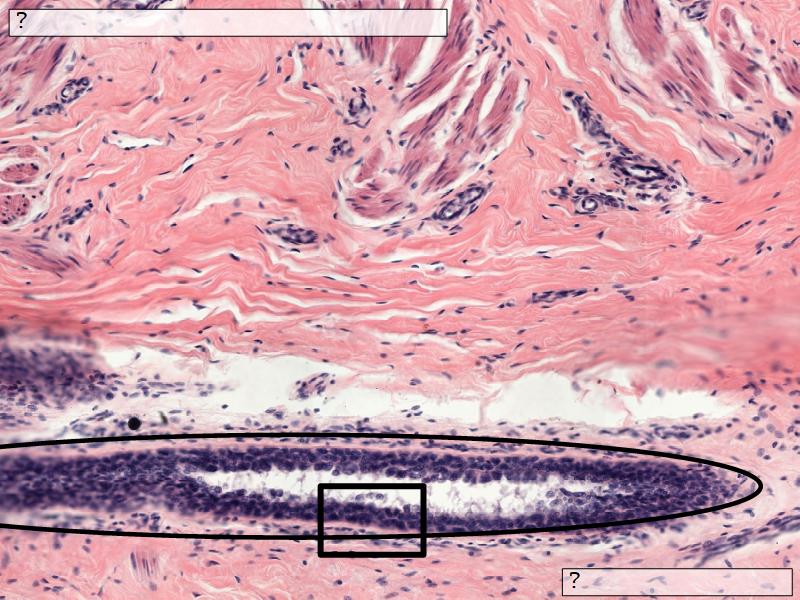

Mammary gland

Write short notes describing the structure of the mammary gland.

(5)

• Compound tubuloalveolar gland

• 12 - 20 glands

• Each with own lactiferous duct

• Each with own lactiferous sinus

• Opens on skin at apex of nipple

Two stages

• Resting

• Active

Resting and active

Describe the resting mammary gland and compare with the active gland.

(8)

Resting gland

• Connective tissue dominate

• More adipose tissue

• Glandular tissue reduced

Active gland

• Terminal ducts expand

• Forms alveoli

• Connective tissue reduced

• Adipose tissue reduced

• Glandular tissue dominate

Structures

List the structures and cells found in the mammary gland.

• Lactiferous sinuses

• Stratified squamous near opening on skin

• Stratified cuboidal other parts

• Lactiferous ducts

• Stratified cuboidal

• Myoepithelial cells

• Underlie lactiferous ducts in most areas

• Basal lamina

• Separate epithelial components from stroma

• Much larger than resting phase

• Terminal ducts proliferate to form alveoli

• Alveoli

• Surrounded by incomplete myoepithelial cells

Alveolar cells

• Apocrine secretion

• Active state

• Resting state